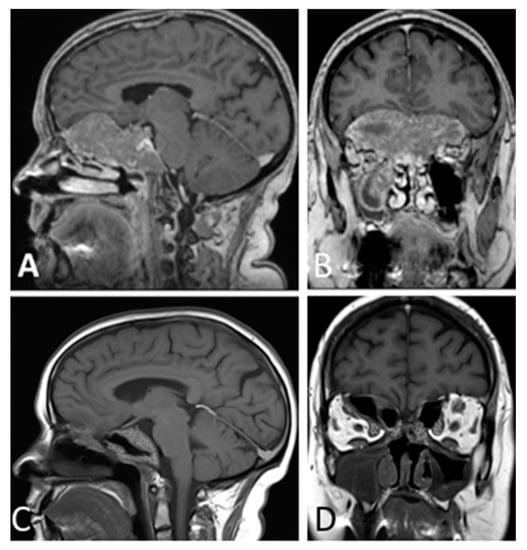

Among the 96 patients included, 55 were men (57.3%) and 41 were women (42.7%), and the mean age was 52.2 years (range 26–81 years). Gender and age were not significantly associated with EoR rate (p = 1.763) or hospital length of stay. Mean cranio-caudal diameter of lesion was 46.5 mm (range 41–61 mm). According to Knosp [8] grading scale, 30 (31.2%) were classified as grade 0; 24 (25.0%) grade 1; 19 (19.8%) grade 2; 9 (9.4%) grade 3 and 14 (14.6%) grade 4. Endocrinological screening confirmed the non-functioning status in all patients included in the study. Seventy-eight patients (81.2%) presented with visual field defects, 9 of whom (9.4%) also had visual acuity impairment. Fifty-three patients (55.2%) presented with various degree of anterior pituitary insufficiency: 27 had panhypopituitarism, 14 had combined corticotropic and thyrotropic insufficiency, 6 had isolated corticotropic insufficiency, 3 had isolated thyrotropic insufficiency and 3 isolated gonadotropic insufficiency. Twelve patients (12.5%) had headaches and 3 (3.1%) presented drowsiness associated with hydrocephalus. According to intraoperative assessment of lesion consistency, 50 GPAs (52.1%) were soft, whereas 46 GPAs (47.9%) were firm/fibrous. Thirty-one GPAs (32.3%) were deemed to have significant vascularization due to profuse intraoperative bleeding impairing visualization through the endoscopic lens and requiring more than 20 mL of advanced hemostatic matrix, whereas the remaining 65 GPAs (67.7%) did not. Interestingly, our results are in keeping with the data reported by previous studies [11,12], confirming that 2/3 of GPAs are not highly vascularized. EoR was classified as follows: GTR in 34 cases (35.4%) (Figure 1), NTR in 12 cases (12.5%) (Figure 2), and STR in 50 (52.1%) (Figure 3 and Figure 4).

Figure 3. T1-weighted contrast-enhanced MR images. Preoperative sagittal (A) and coronal (B), views showing a giant pituitary macroadenoma, Knosp grade 4. Three-month postoperative coronal (C) and sagittal (D) views showing STR with residual tumor in both cavernous sinuses.